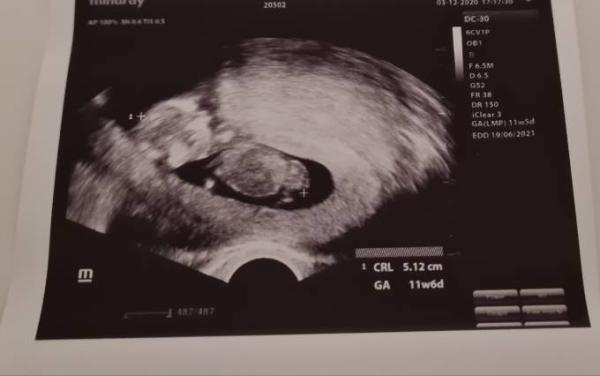

Wir hatten gestern auch wieder die nächsten Vorsorgeuntersuchung und dieses Mal durfte mein Freund sogar mit. Unser Baby hat sich von seiner besten Seite gezeigt, fleißig gestrampelt und es sah aus, als würde es krabbeln Wir sind so verliebt in diesen kleinen zwerg. Inzwischen ist unser Wunder 5,1cm groß, das Herz schlägt ordentlich und die Bewegungen sind auch perfekt. Zum Geschlecht konnte und wollte meine Ärztin noch nichts sagen, das war mir aber auch klar. Der ET wurde vom 21.06.21 nun auf den 18.06.21 verschoben. Mal gucken... Vielleicht bekommen wir nächste Woche bei der Nackenfaltenmessung mehr Infos.

Bild zu Gestern Vorsorge - Forum für Juni - Mamis